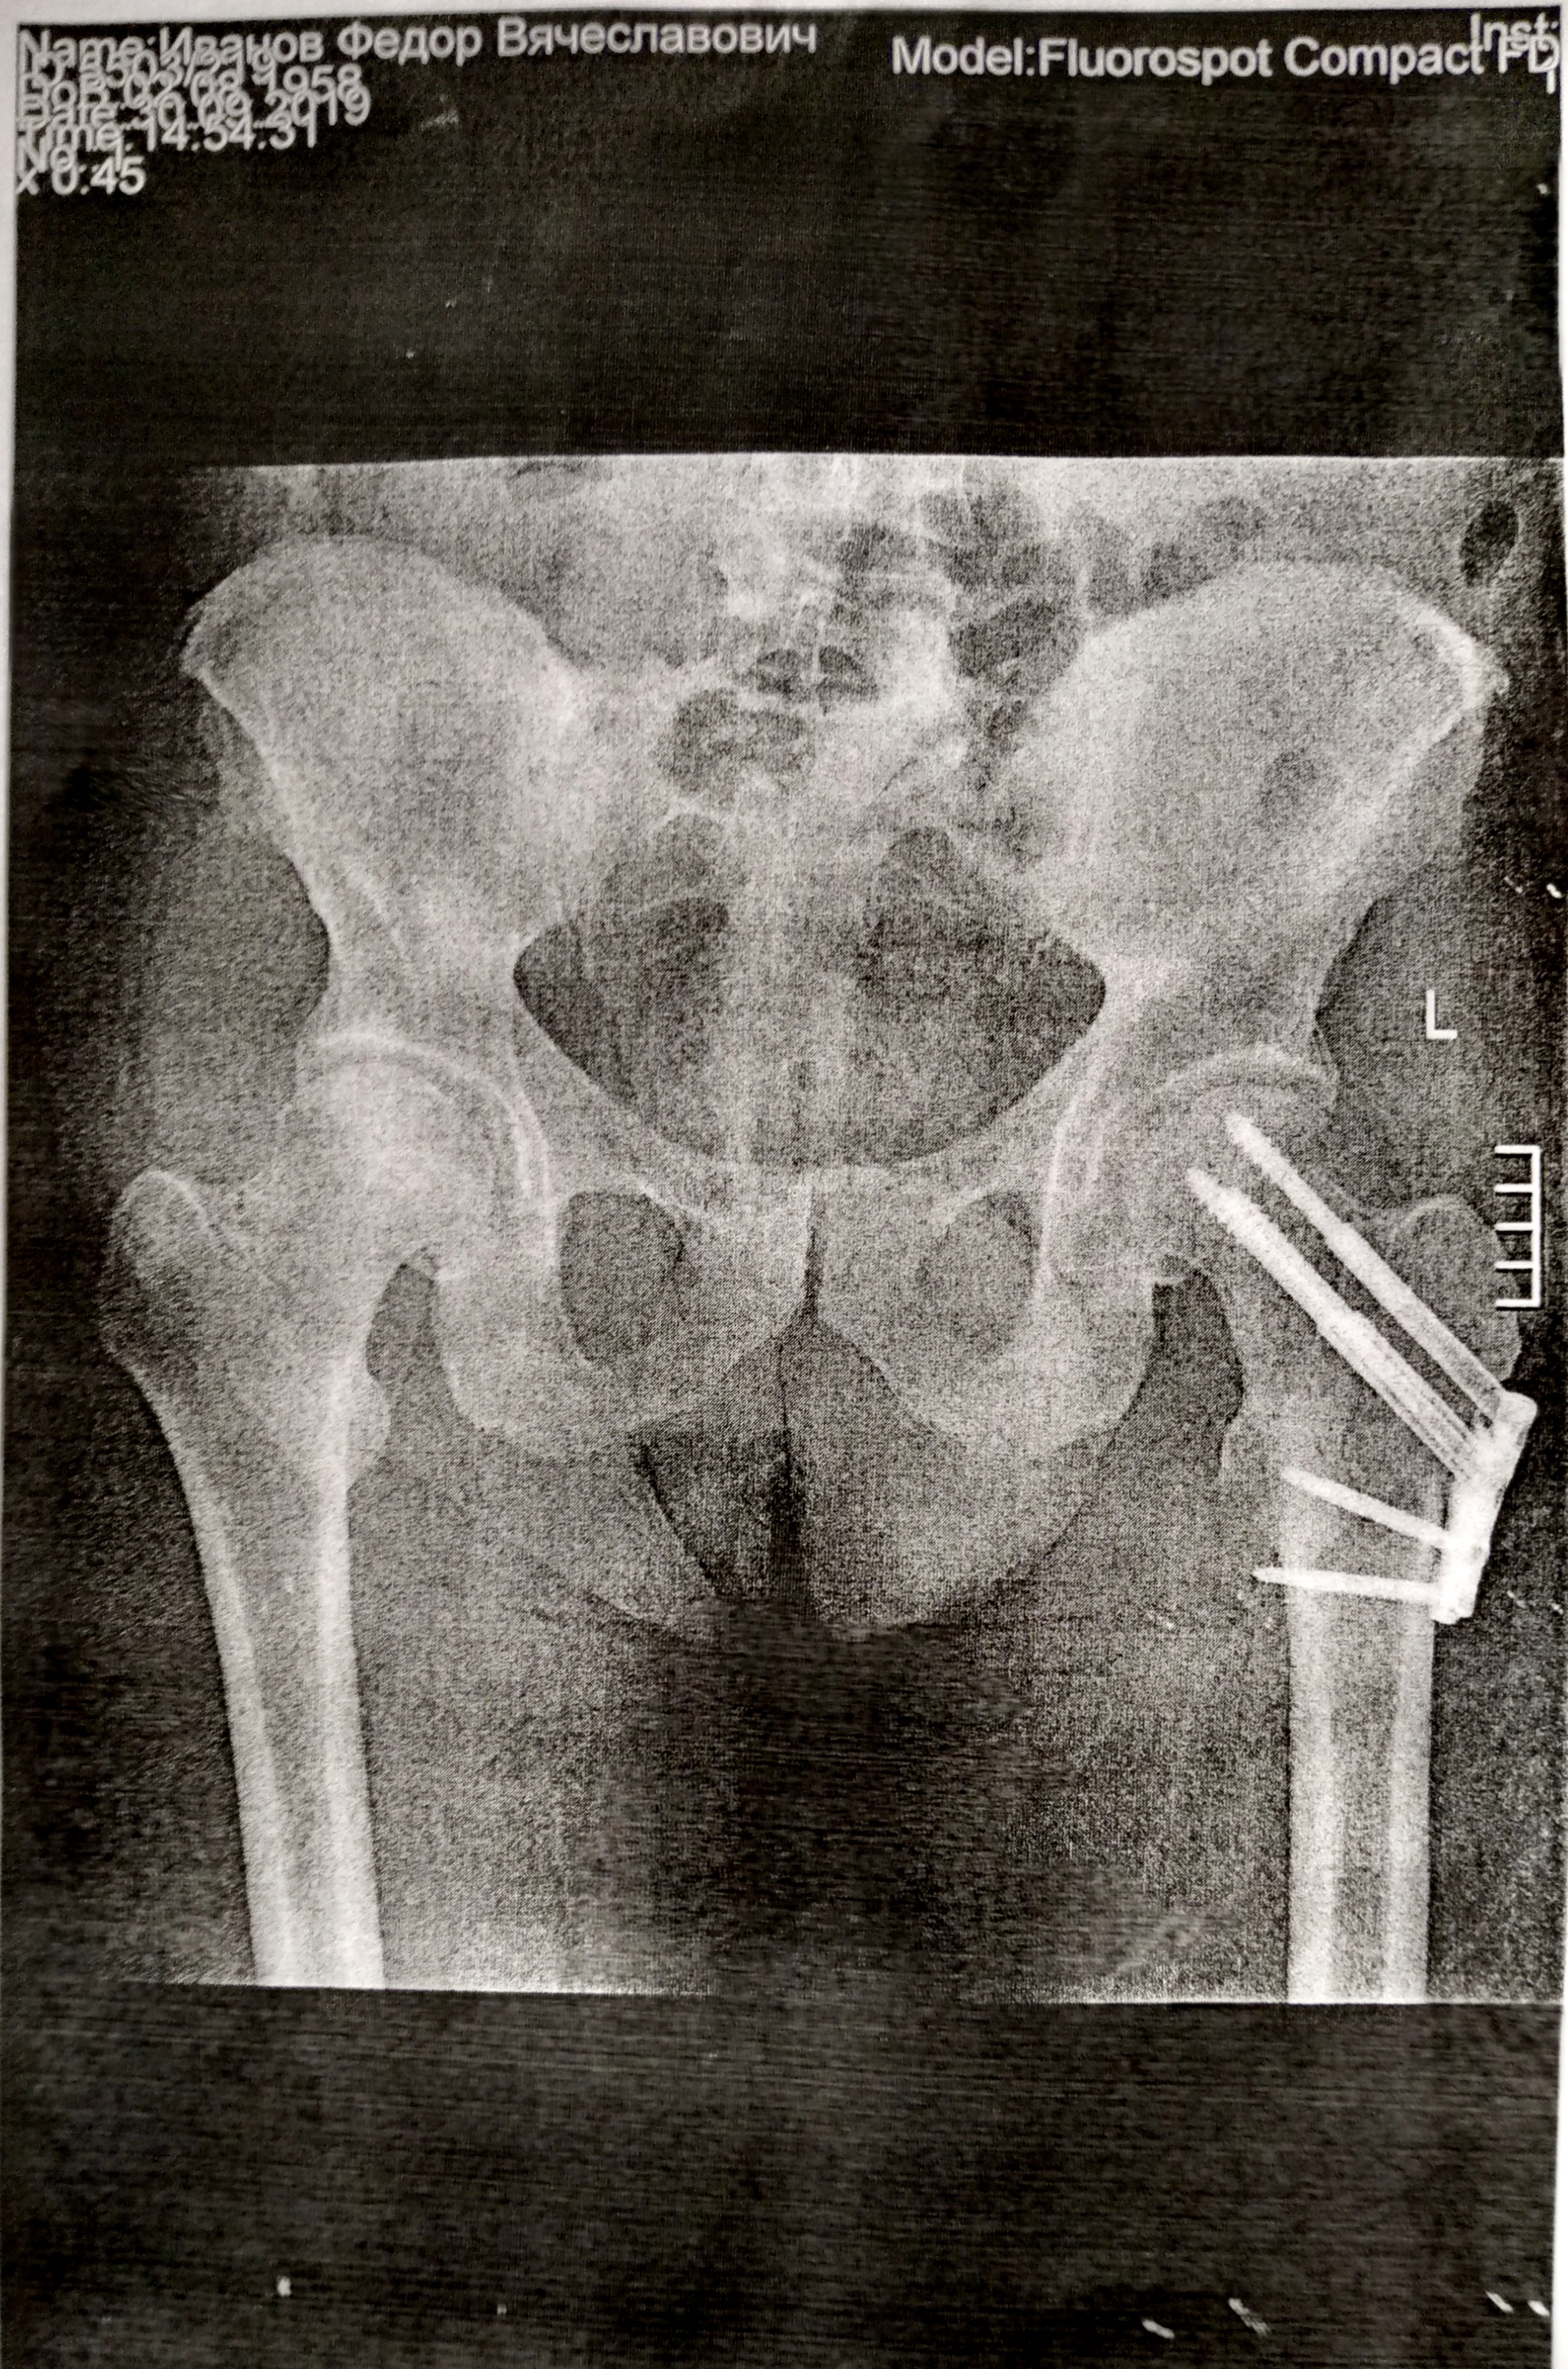

А что, тебе шейку умудрились привинтить? Это что-то новое в травматологии.

Наглядно показываю... конкретный перелом, даже с небольшим смещением... выправили вот так: